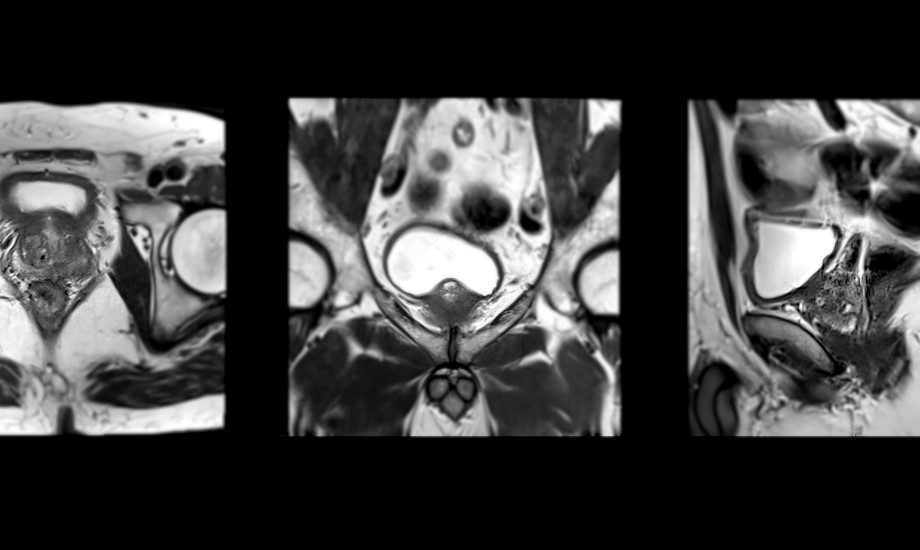

Seit 2021 empfehlen S3- und EAU-Leitlinien das multiparametrische MRT (mpMRT) der Prostata zur Primärdiagnostik des Prostatakarzinoms. Doch wie sieht die tatsächliche Versorgungsrealität bei uns aus?

© samunella / stock.adobe.com